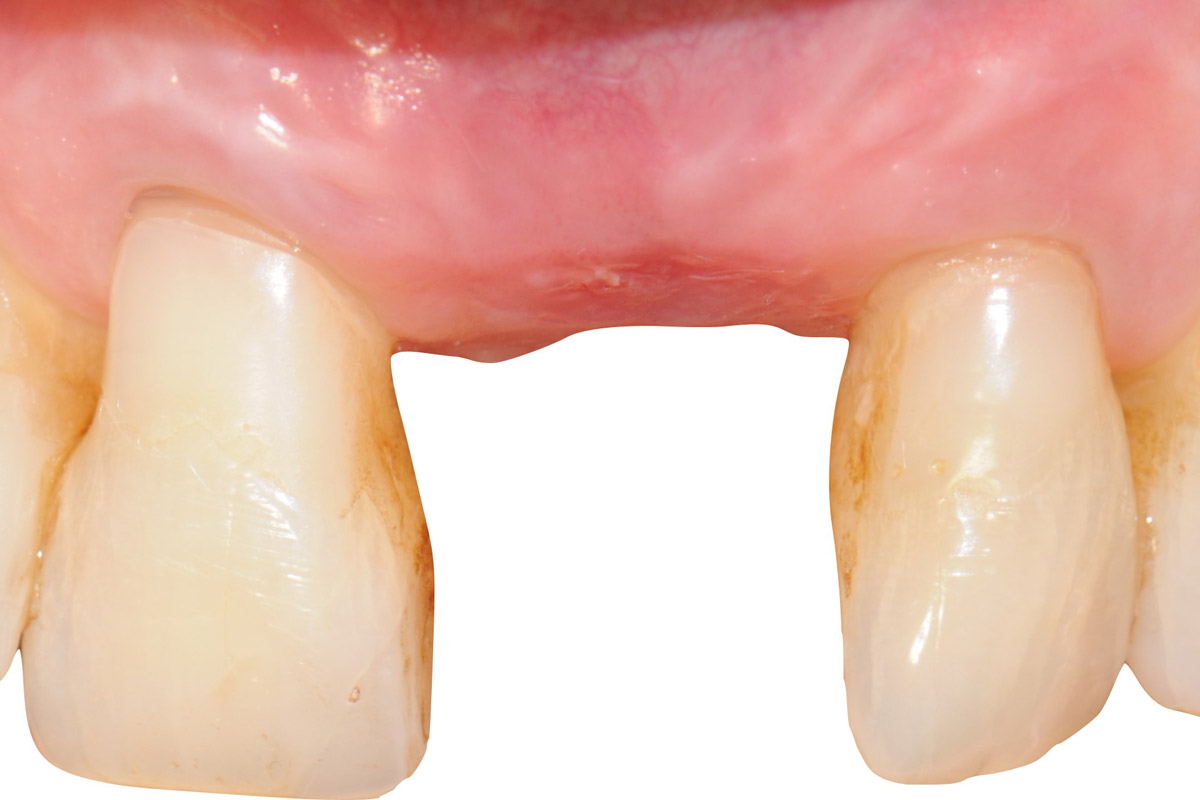

1/18 - Initial clinical situation showing strongly compromised tooth 21Tooth extraction and socket sealing with mucoderm® - Dr. A. Rossi

Initial clinical situation showing strongly compromised tooth 21